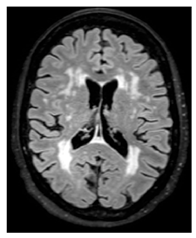

| White matter hyperintensity: | White matter demyelination resulting from multiple pathological insults including: chronic hypoperfusion, blood–brain barrier leakage, impaired amyloid clearance, and iron deposition [28] | ![]() | Variable in size Hyperintense: FLAIR, T2, and T2*-GRE Hypointense: T1 Isointense: T1 |